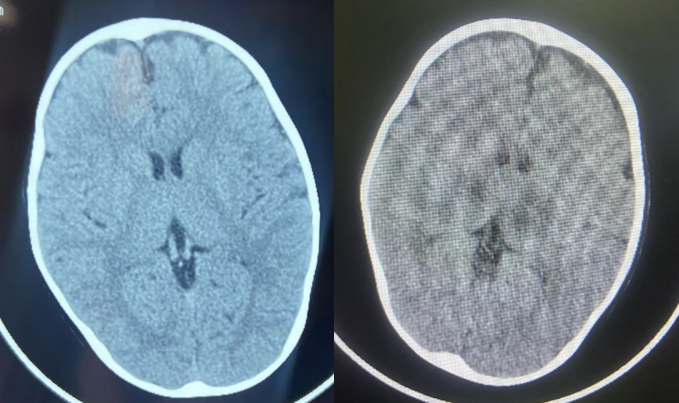

神经内科副主任张建昭凭借丰富经验,在首次CT无典型病变情况下,根据升高的肝酶敏锐察觉异常,果断要求复查头颅CT。仅仅 8 小时后,复查结果显示双侧丘脑肿胀,急性坏死性脑病可能性极大。这种疾病起病急、进展快,死亡率高达 30%-50%,每一分延误都可能造成不可逆脑损伤。

显示双侧丘脑在8小时内发生的改变。左为入院前头颅CT;右为入院当日复查的头颅CT